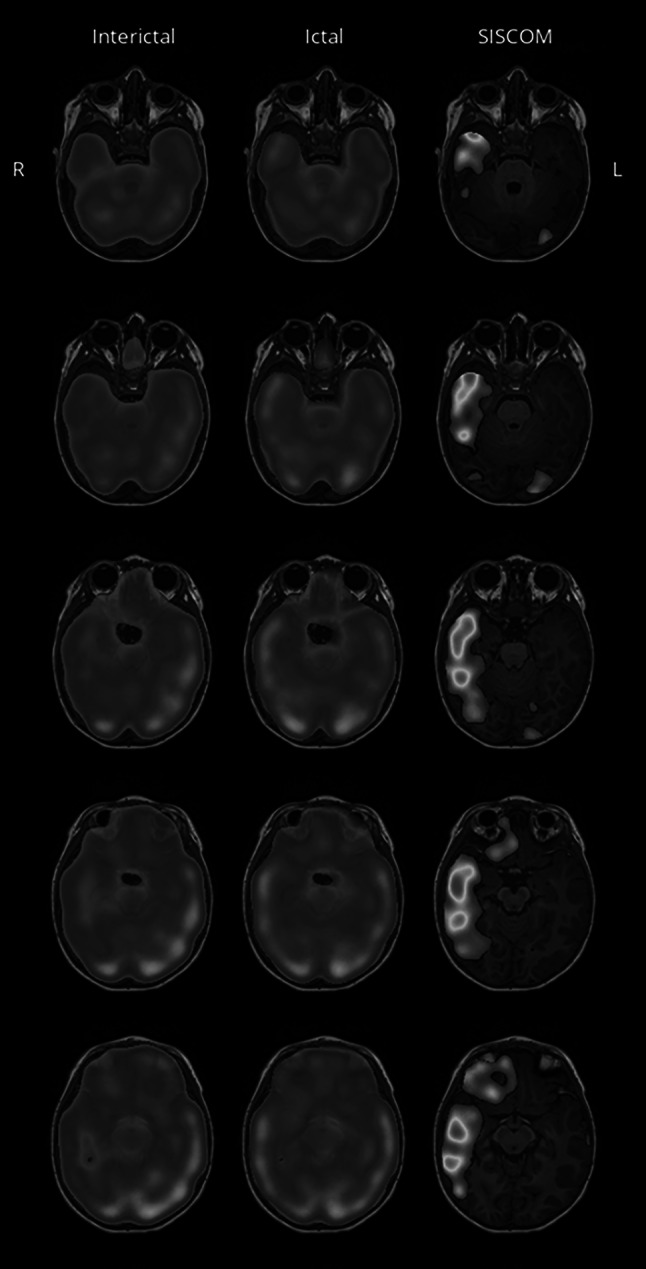

Fig. 2.

Example MRI panel result file generated by MNI SISCOM showing interictal/ictal SPECT and SISCOM results side-by-side. This figure shows only 5 consecutive slices out of 23 axial slices with 5 mm thickness. Coronal and sagittal panels are also generated, but not shown here